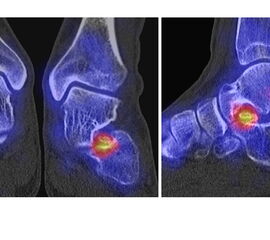

Abbildung 1.8.a und b: Akute Arthritis bei bekannter Gicht in beiden OSG: links die Früh-/Weichteilphase; rechts die Mineralisations­phase. Deutliche, entzündlich bedingte Mehranreicherungen in der Früh-/Weichteilphase. In der Mineralisation­sphase erkennt man die entzündliche Mitreaktion der subchondralen Gelenkabschnitte.

Abbildung 1.8.c - e: Akute Arthritis in beiden OSG, rechts > links. Im SPECT/CT erkennt man die Mitreaktion der subchondralen Gelenkabschnitte. Die Arthritis ist so akut, dass (noch) keine ossären morphologischen Veränderungen im CT abgrenzbar sind.